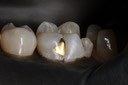

Wes Sato #14 casting